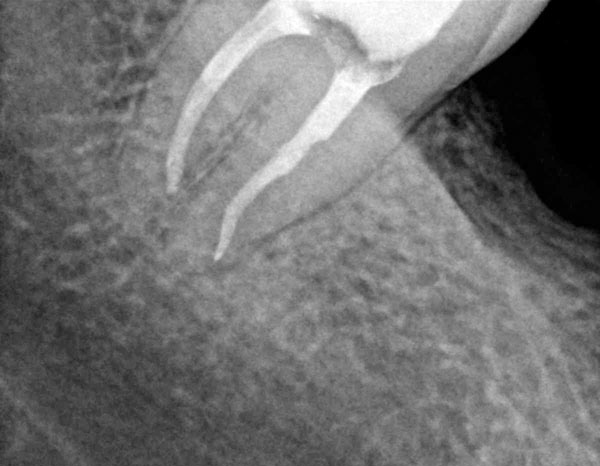

Upalu oko vrha korijena (tzv. "granolom") uspješno liječimo endodontskim liječenjem koje podrazumijeva čišćenje, dezinfekciju i punjenje korijenskih kanala. Zahvat je jednostavniji na jednokorijenskim zubima (npr. sjekutićima), a puno zahtjevniji na kutnjacima koji najčešće imaju četiri korijenska kanala.

Donji desni umnjak prije i poslije endodontskog liječenja